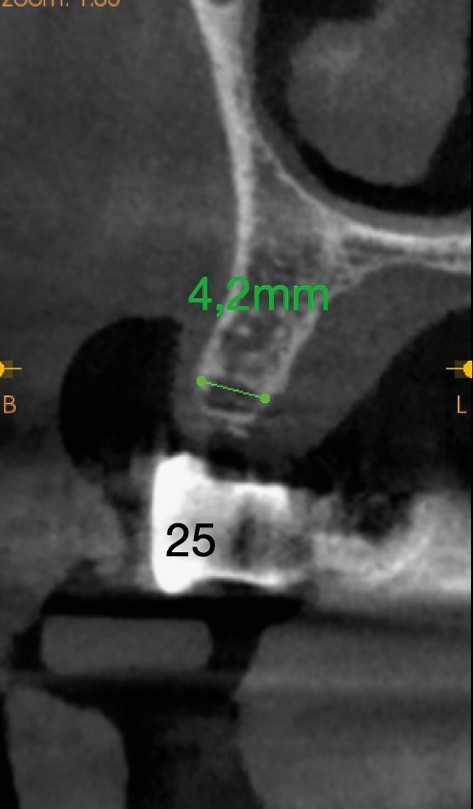

Concernant le secteur 2, le site 25 présente une crête osseuse fine nécessitant une régénération osseuse guidée (ROG) afin de pouvoir poser un implant dans de bonnes conditions (fig. 1).

- deux implants, situés en 25 et 27 avec une ROG sur le site de la 25,

- deux implants, situés en 26 et 27 avec extension mésiale en 25.